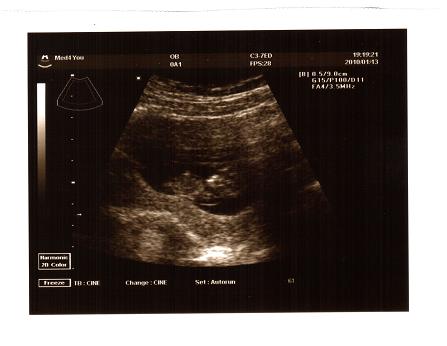

küldöm a nevem priviben, én is nagyon kíváncsi vagyok Rátok!!! Holnap ismét láthatod a kis picurkát, drukkolok, hogy minden rendben legyen!!!!